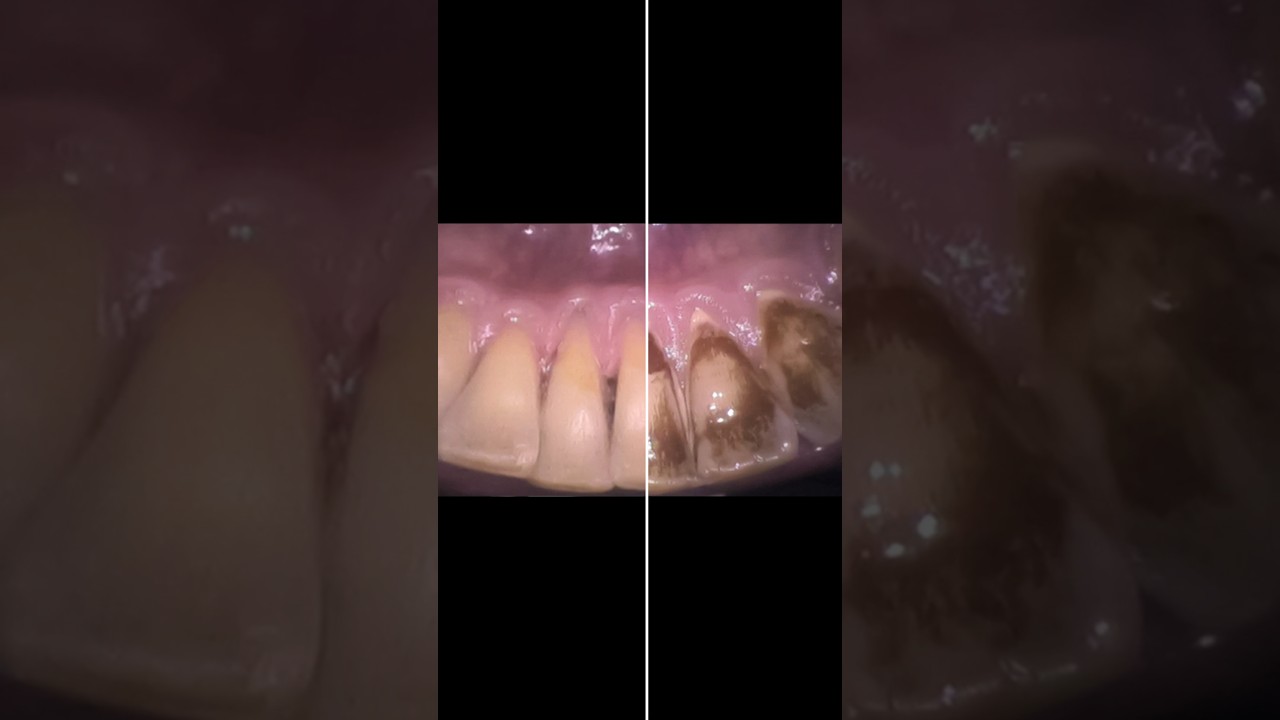

Скачать или смотреть Smile Transformation at Mint Dental Hygiene Takapuna! Watch Nova Edgcombe's expert care in action!

Smile Transformation at Mint Dental Hygiene Takapuna! Watch Nova Edgcombe's expert care in action!